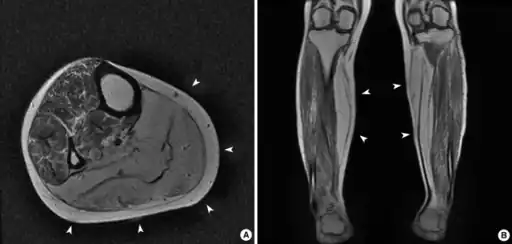

On examination of muscle biopsy material, the nuclear material is located predominantly in the center of the muscle cells, and is described as having any "myotubular" or "centronuclear" appearance. In terms of describing the muscle biopsy itself, "myotubular" or "centronuclear” are almost synonymous, and both terms point to the similar cellular-appearance among MTM and CNM. Thus, pathologists and treating physicians use those terms almost interchangeably, although researchers and clinicians are increasingly distinguishing between those phrases.

In general, a clinical myopathy and a muscle biopsy showing a centronuclear (nucleus in the center of the muscle cell) appearance would indicate a centronuclear myopathy (CNM). The most commonly diagnosed CNM is myotubular myopathy (MTM). However, muscle biopsy analysis alone cannot reliably distinguish myotubular myopathy from other forms of centronuclear myopathies, and thus genetic testing is required.Diagnostic workup is often coordinated by a treating neurologist. In the United States, care is often coordinated through clinics affiliated with the Muscular Dystrophy Association.